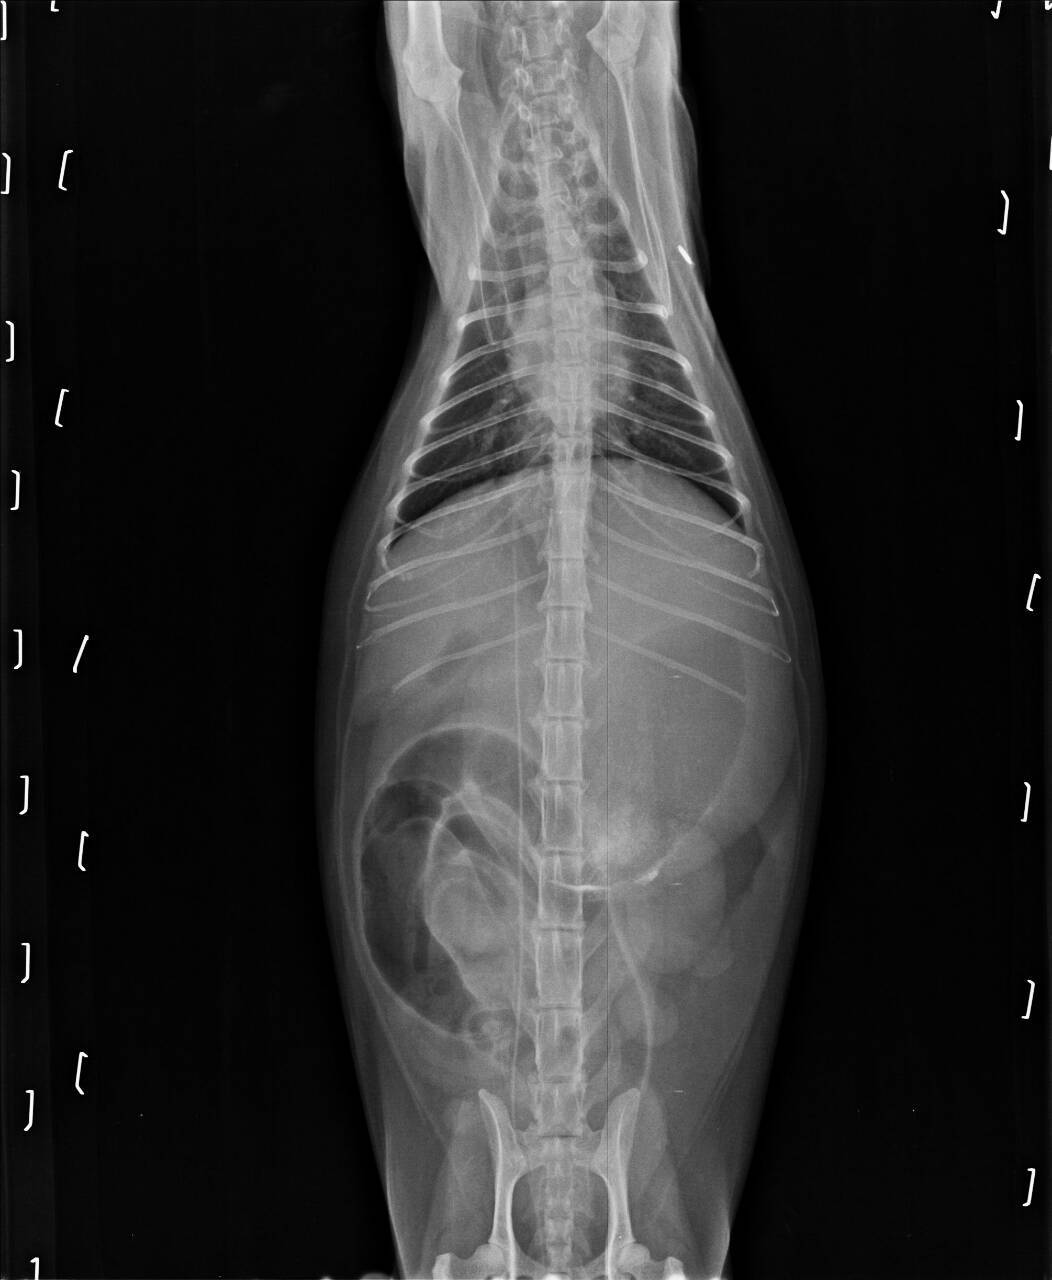

主題: 敦化北路路倒貓 申請者姓名: 王顥潔 花色: 申請日期: 2015-04-09 22:12:20 申請者部落格: 申請者臉書網址: 所在縣市/合作醫院: 台北市/極光動物醫院 治療費用: 30654元 需求人數: 33人 已結案 (2021-09-03 23:51:28) 報名人員: Jun Ish x2(已付款)、恰吉吉 x2(已付款)、Patrick x10(已付款)、Belle(已付款)、Bella Lin(已付款)、Norman Wu(已付款)、林嘉南(已付款)、amency(已付款)、高賽、咪咪靜(已付款)、kawolu(已付款)、戴戴(已付款)、Leo Chung x10(已付款)、JOJO(已付款)、 候補人員: joyce、 動物病情說明: 於3/22半夜在台北市松山區敦化北路155巷發現病懨懨路倒貓咪咪,有剪耳,是TNR的貓咪。先安置家裡,隔天送仁心檢察驗血後,發現血糖很高,有黃疸,腎衰竭,以及急性胰炎,白血球五萬以上。

在仁心動物醫院住院及施打藥物搶救治療,因為醫療費用龐大,無以為繼,經與tnr協會通報,感謝協會協助轉往極光醫療。

後續醫療費用,懇請協會准予申請醫助,感恩。動物近況說明: 04/03/22晚上撿到。

104/03/23 送仁心動物醫院。

體溫36.6(晚上回溫到38度)

白血球五萬多

高血糖

FPL陽性

貓愛滋、白血病陰性

Bun大於130

肝指數 8

體重3.8公斤

3/24蒙協會幫助,轉院極光動物醫院,因有脂肪肝,插鼻胃管餵食。

104/03/24

白血球48,000

肝指數5.5

胰臟炎,黃疸。

插鼻胃管,無法站立。

104/03/25

白血球43,000

肝指數7.6

無法站立,當晚施打血漿。

數值有下降一些,但血壓仍偏低,但這兩天的觀察算是不樂觀中的穩定。

104/03/26

醫院通知咪咪需要血漿

早上七點一度休克

白血球飆6萬

肝指數9.6

血壓50

中午12點時,咪咪吐了

沒多久即往生……

實在感到非常遺憾跟難過,咪咪還是無法撐過這個難關,感謝協會幫助咪咪的醫療費用,更謝謝捐款人您的大愛。